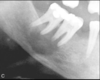

What are these radiographic findings?

Residual Cysts

What is the radiographic finding?

Residual Cyst